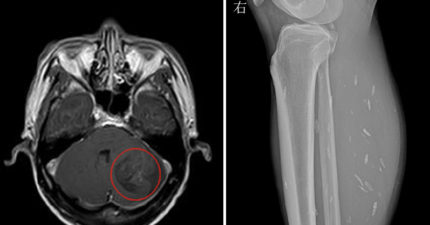

他平常狂吃「半熟猪肉」,医生打开他的X光片差点呕吐「肌肉组织里的小白点会要你的命!」